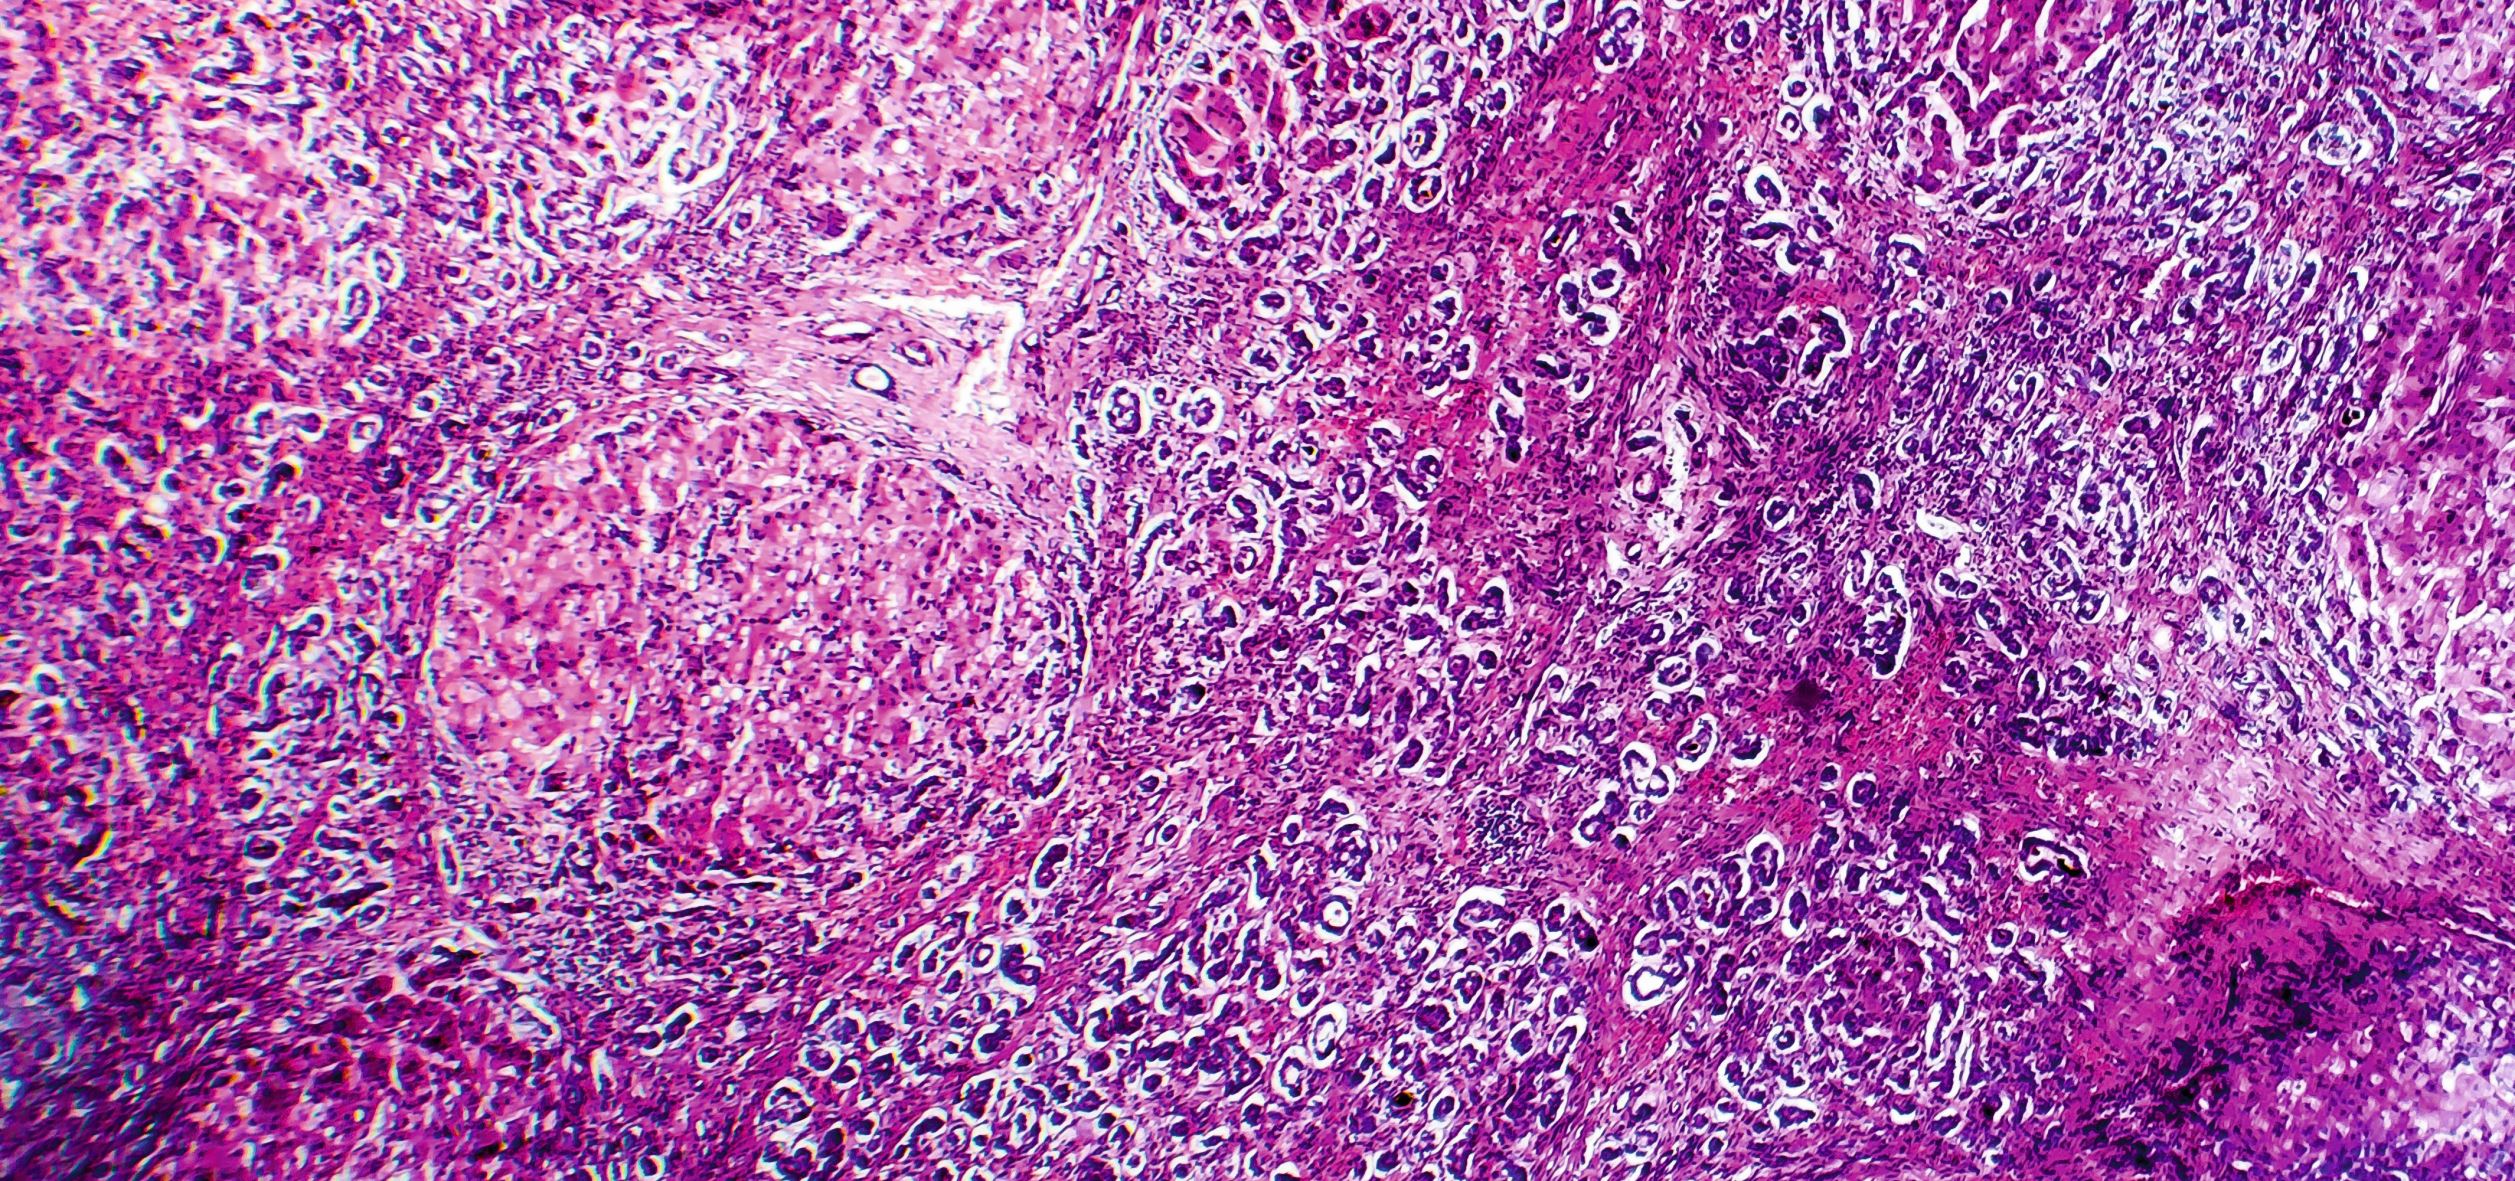

Zu den häufigsten autoimmunen Lebererkrankungen zählen die autoimmune Hepatitis, die primär biliäre Cholangitis und die primär sklerosierende Cholangitis. Eine neue S3-Leitlinie gibt nun Aufschluss über die aktuellen Empfehlungen zur Erkennung und Therapie.

Histopathologie der biliären Zirrhose/© Dr_Microbe / stock.adobe.com, Ärztin tastet Bauch eines Patienten ab/© (M) qunica.com / Stock.adobe.com (Symbolbild mit Fotomodellen)